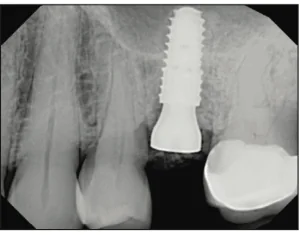

INTRODUCTION Reconstruction of edentulous areas with dental implants is a viable alternative to conventional dental procedures and has become rather mainstream within the profession and